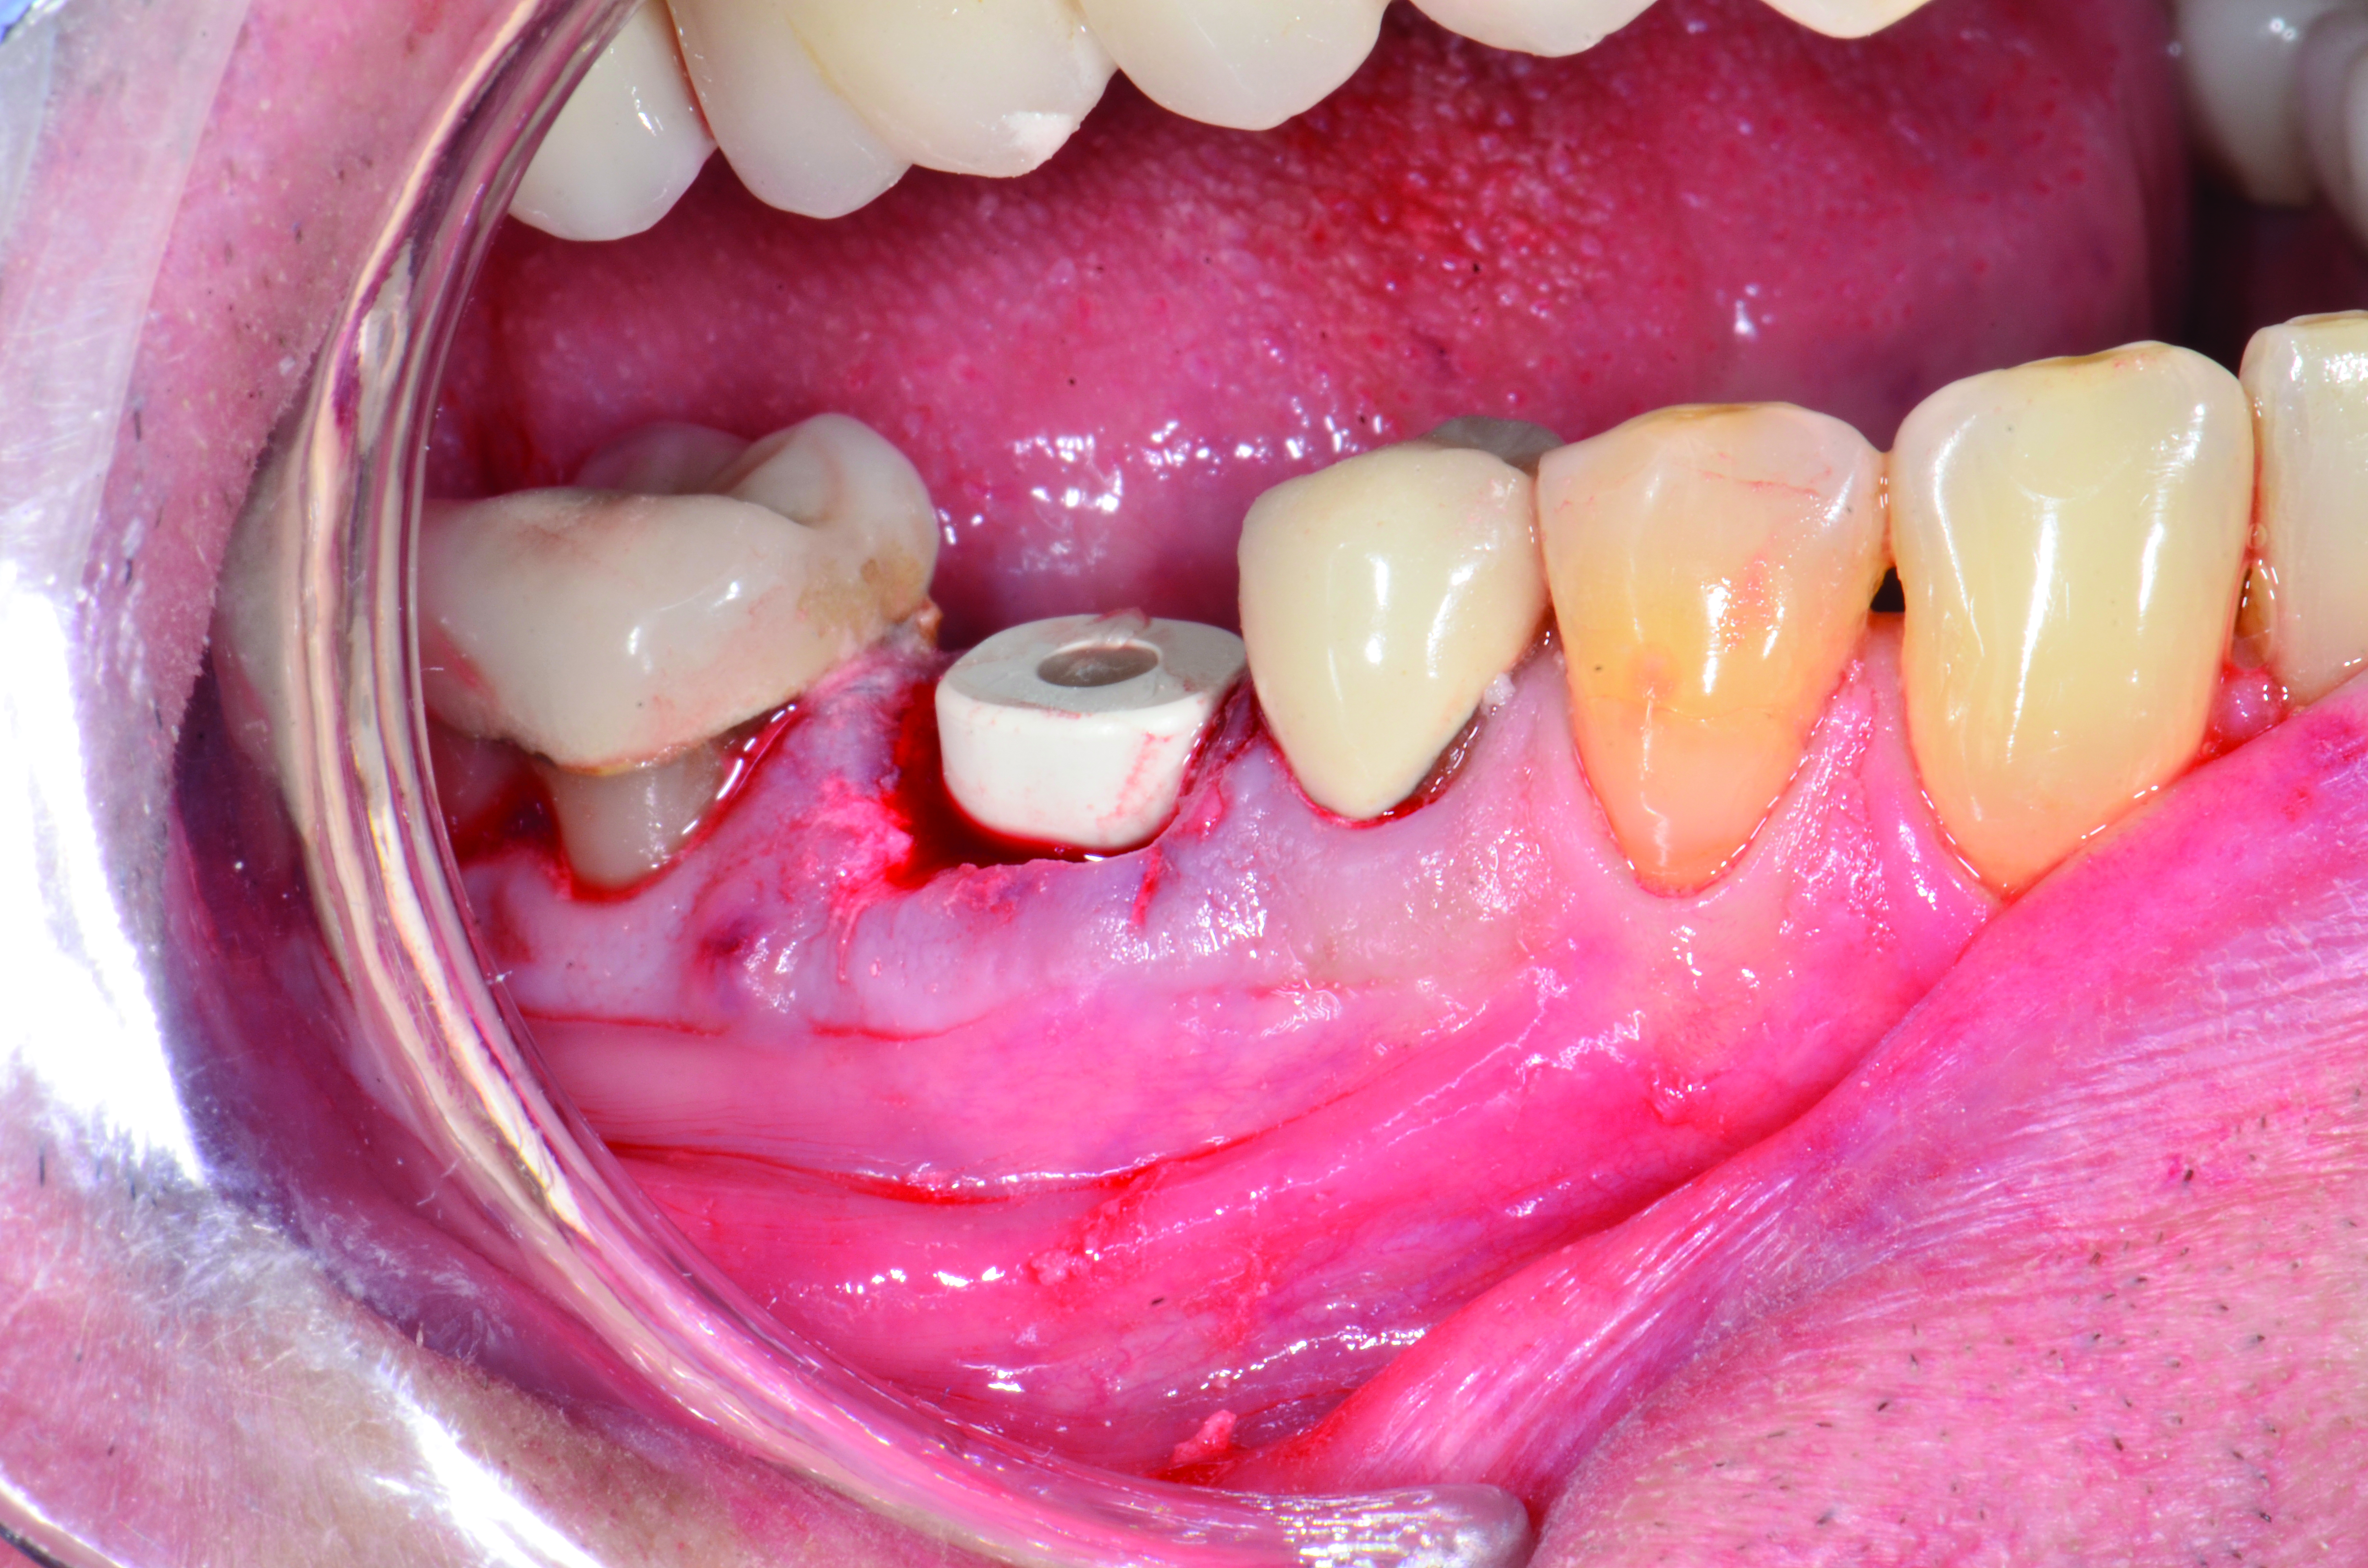

Fig 4. Intraoral scanning with digital impression scanner.

Figure 4

A mandibular right first molar was extracted due to an advanced Class III furcation and an irreversible pulpitis—a combination lesion. An immediate implant placement protocol was elected, and a PEEK abutment was placed on the implant (Figure 1). After 3 months of healing, a scan body was placed on the osseointegrated implant (Figure 2 and Figure 3), and an intraoral scan was taken (TRIOS Pod) (Figure 4) for the fabrication of a screw-retained crown.